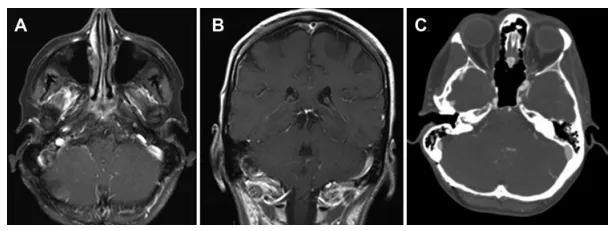

病理分析结果符合WHOⅠ级脑膜瘤。术后影像显示肿瘤全切除,横窦及乙状窦通畅(图3)。术后2.5年随访影像学检查未见肿瘤复发征象。

病例2,术后轴位(A)与冠状位(B)增强T1加权磁共振图像显示右侧后颅窝脑膜瘤已实现大体全切除。术后轴位脑CT血管成像(C)显示右侧乙状窦通畅。